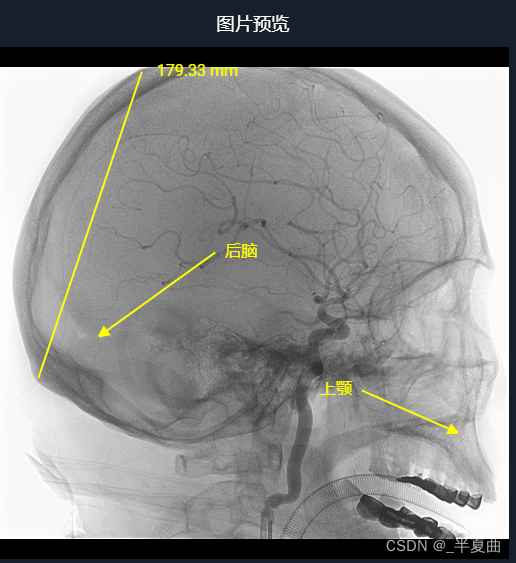

Dicom影像在线查看,提供测量、窗口调整、平移与缩放、图像截图、注释等工具;